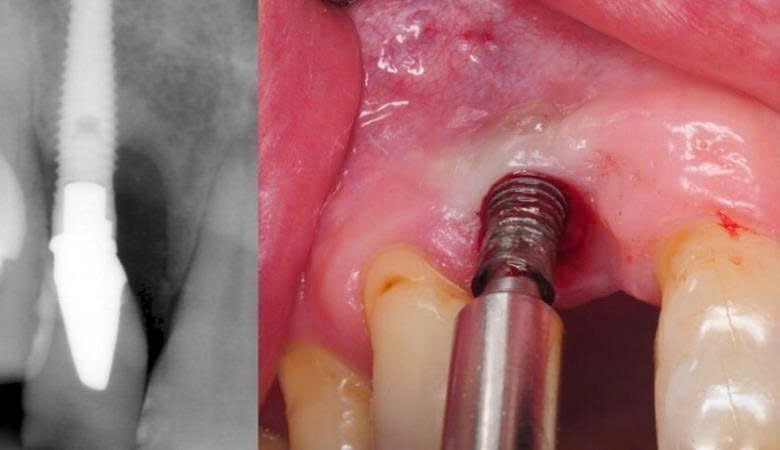

2. Trụ Implant bị đào thải

Sự tích hợp xương là yếu tố quyết định thành công của Implant. Trụ giá rẻ thường làm từ vật liệu không đạt chuẩn, không tương thích sinh học, dễ bị đào thải. Tay nghề bác sĩ non kém cũng khiến trụ đặt sai vị trí, không ổn định và thất bại sau thời gian ngắn.